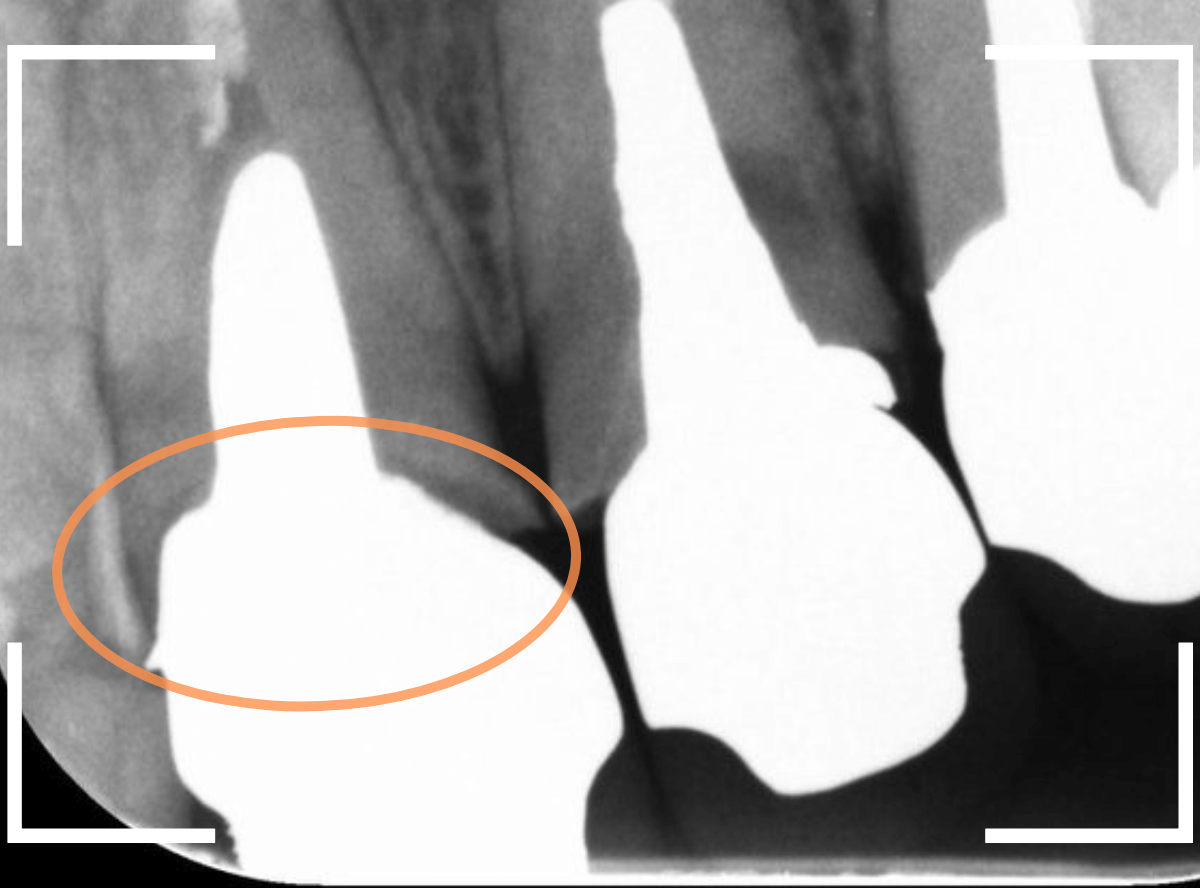

レントゲン写真で確認します。

隣のさし歯も、ですが、さし歯の縁が見えないところで不適合になっています。

これでは、いくら歯ブラシを頑張っても、汚れがたまってしまい、歯肉の改善ができません。

歯肉にぴったりあったさし歯に作り直す必要があります。